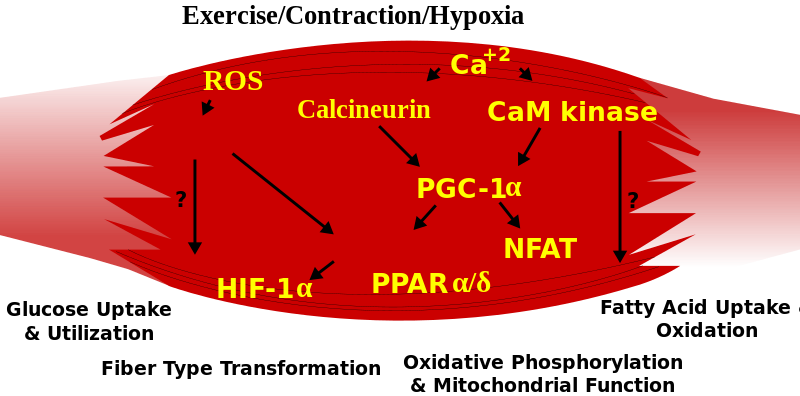

4 – Definitions: hypoxemia, hypercapnea, hypoxia, (an informative/summary figure can be made using Bio-render)

Hypoxia – is a condition involving abnormally low levels of oxygen in body tissues. It can lead to bluish skin, confusion, difficulty breathing, restlessness and fast heart rate. Hypoxia is different to hypoxemia as hypoxia is low oxygen levels in tissues whereas hypoxemia is low oxygen levels in blood.